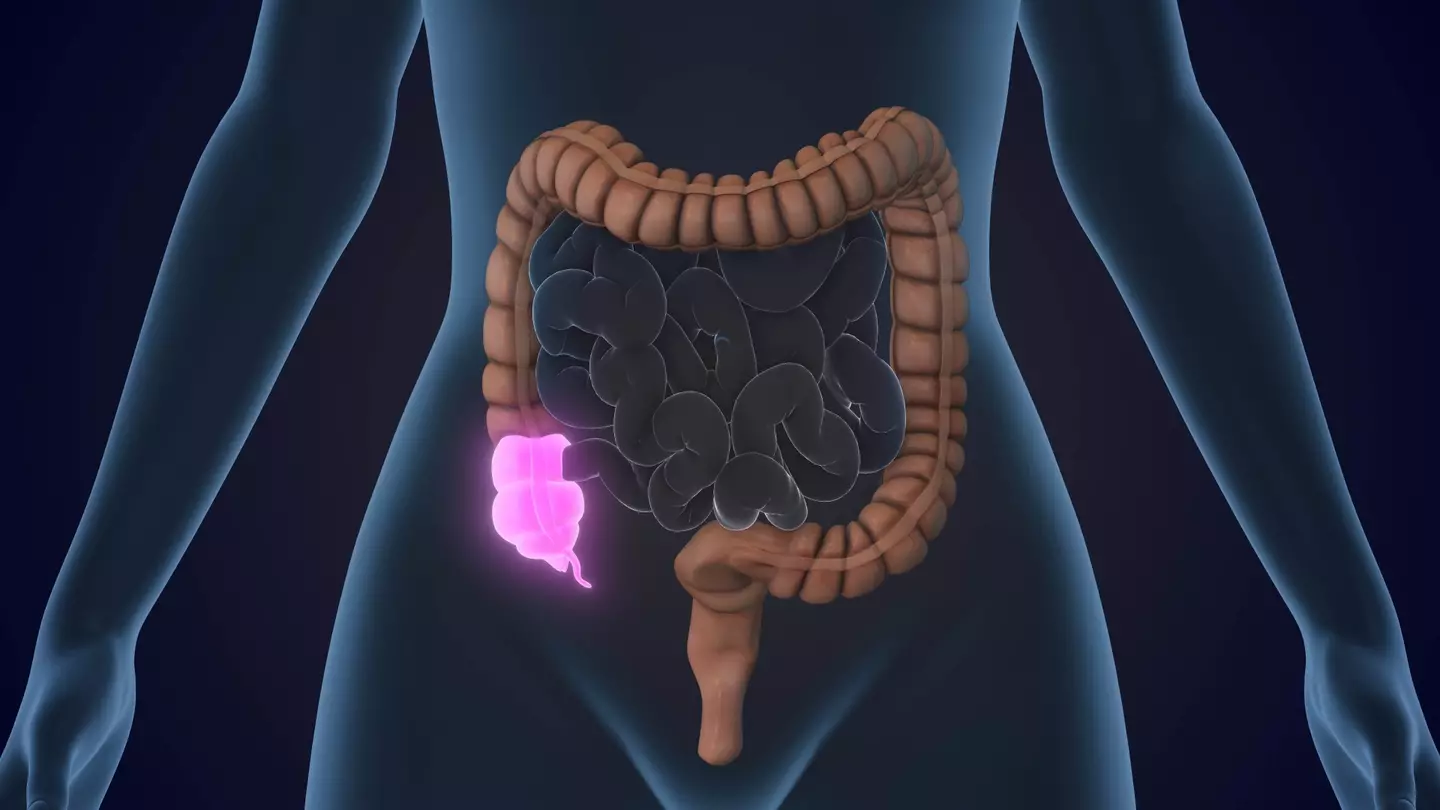

The appendix, which is a small portion of your digestive system, is sat on the lower right side of your abdomen.